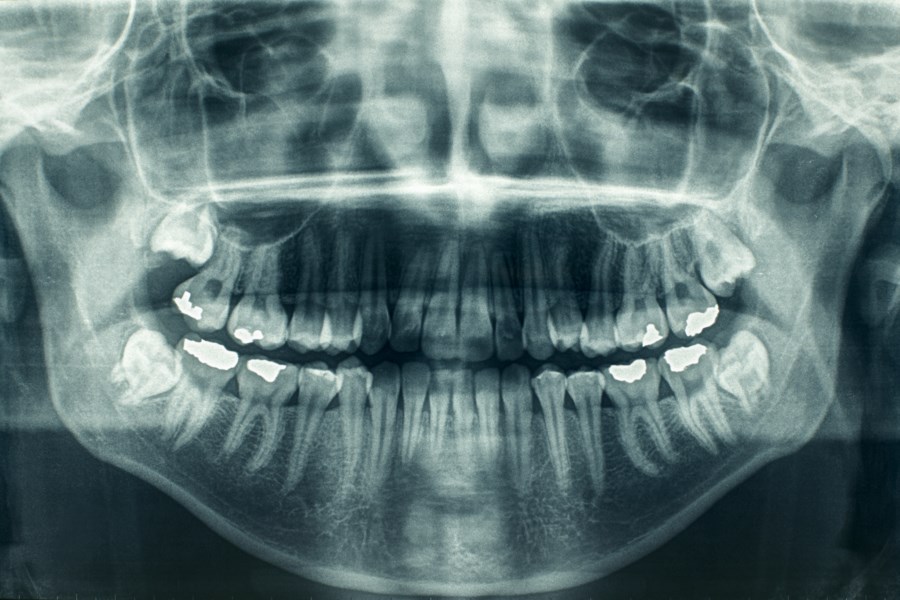

Oral Diagnosis and Radiology

"At our clinic, patients who want to receive an examination and treatment are first given an anamnesis form, followed by an extraoral and intraoral clinical examination."